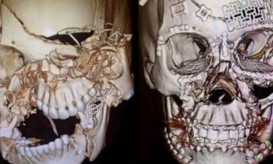

Η φωτογραφία που βλέπετε απεικονίζει το «πριν» και το «μετά» της εκτενούς αναδόμησης κρανίου στην οποία υποβλήθηκε μια γυναίκα,...